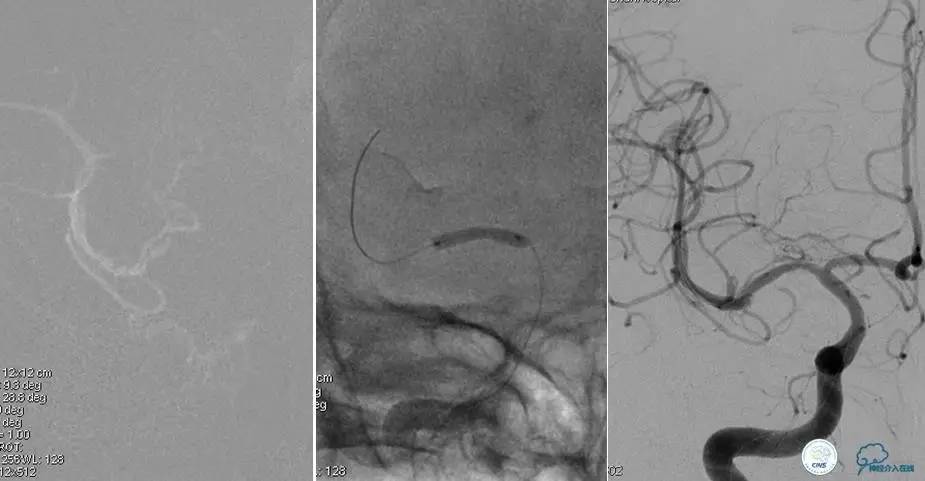

造影评价血管、判断闭塞段,微导丝谨慎穿过闭塞段,微导管造影,交换技术,球囊扩张,Enterprise支架。在后扩张时导丝刺破M3段血管,蛛网膜下腔出血(SAH)。

微导管进入破裂血管,栓塞弹簧圈1枚,出血停止,结束手术。继续双抗,术后2天肌力2级,神经功能恢复明显加快。

术后即刻和6天后CT,患者无明显临床症状。

半年后复查造影,无支架内再狭窄,可见弹簧圈,患者恢复至自己柱杖行走。